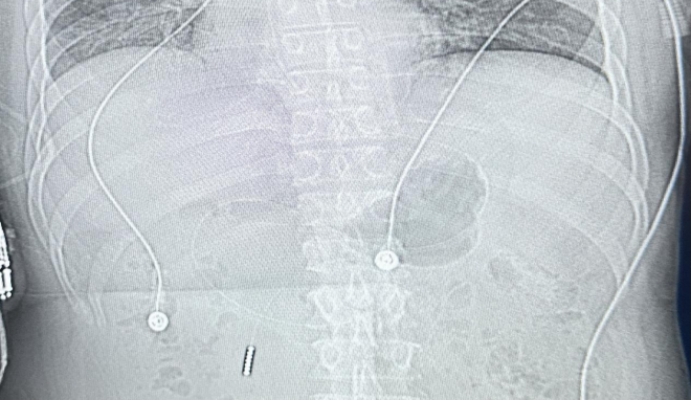

为保障患者安全营养供给,由重症医学科护士长王月华带领护理团队精准实施床旁盲插鼻肠管术。团队术前充分评估患者整体状况,制定周密置管方案;术中规范操作、精准定位;术后及时进行拍片确认,全程仅用时20分钟,操作高效、顺利、安全。